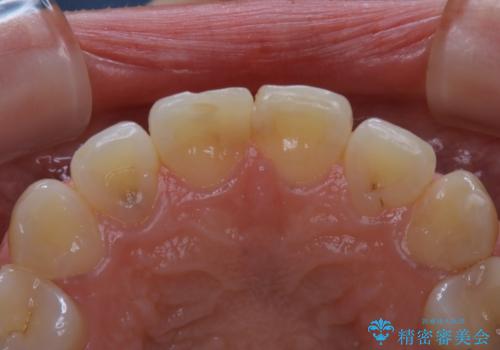

何度も欠けてしまう前歯を被せ物で治療

- プラスチックで治療している前歯が何度も欠けてしまうとお悩みで来院された方です。

歯全体を覆うクラウンにて治療を行いました。

前歯1本のみの被せ物治療を行う場合、他の歯を参考に歯の色や形を忠実に再現することが重要です。オールセラミッククラウン(スペシャル・エクセレント)は、事前に歯科技工士との打ち合わせを行うことで、歯の色や形、さらには患者様のご希望も聴取したうえでクラウンを作製することが可能です。